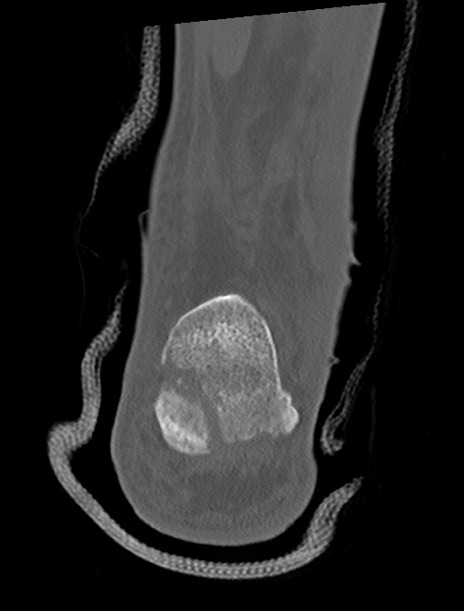

横断像